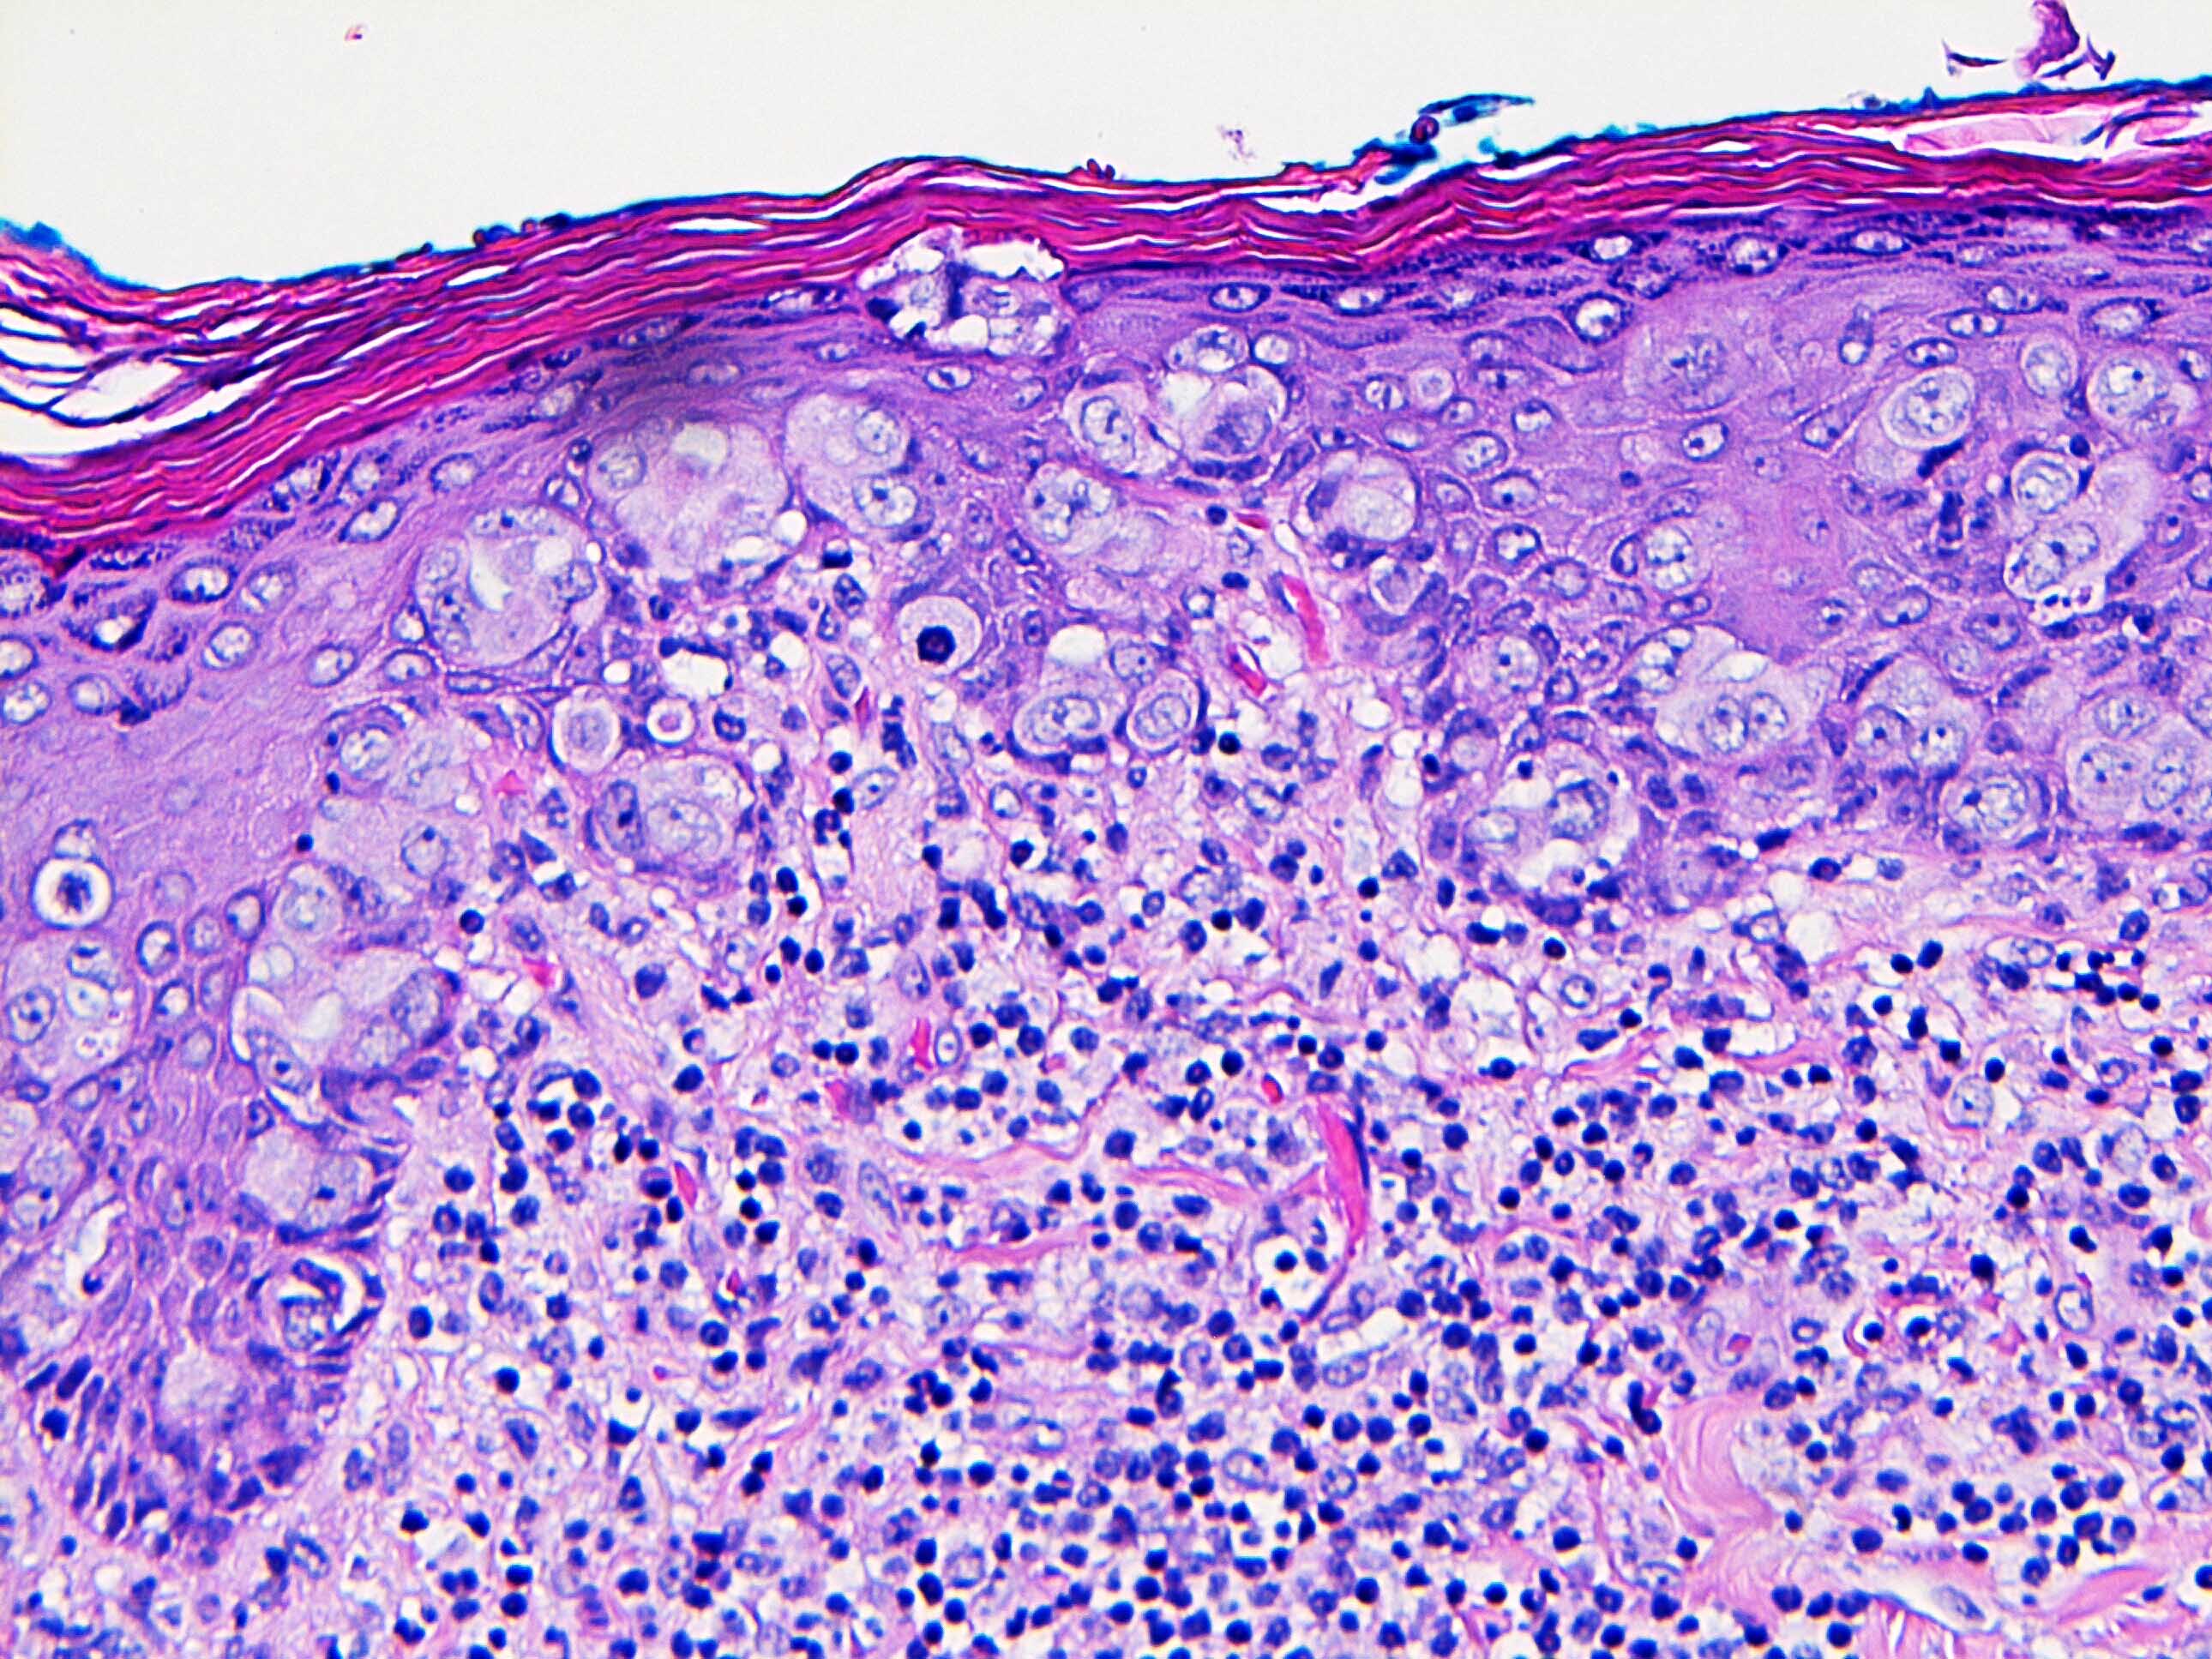

- Single cells or clusters of cells spread throughout the epidermis

- Cells have abundant pale cytoplasm, large irregular nuclei with prominent nucleoli

- Underlying dermis may have chronic inflammation

- Epidermis with hyperkeratosis and possibly ulceration

- Florid cases can show gland formation

- Paget cells may phagocytose melanin, mimicking melanocytes

- Underlying carcinoma is most commonly high grade invasive carcinoma of no special type (NST; 53 - 64%) or DCIS (24 - 43%) (Histopathology 2020;77:181)

Microscopic (histologic) images

Contributed by Anna Biernacka, M.D., Ph.D. and Mary Ann Gimenez Sanders, M.D, Ph.D.